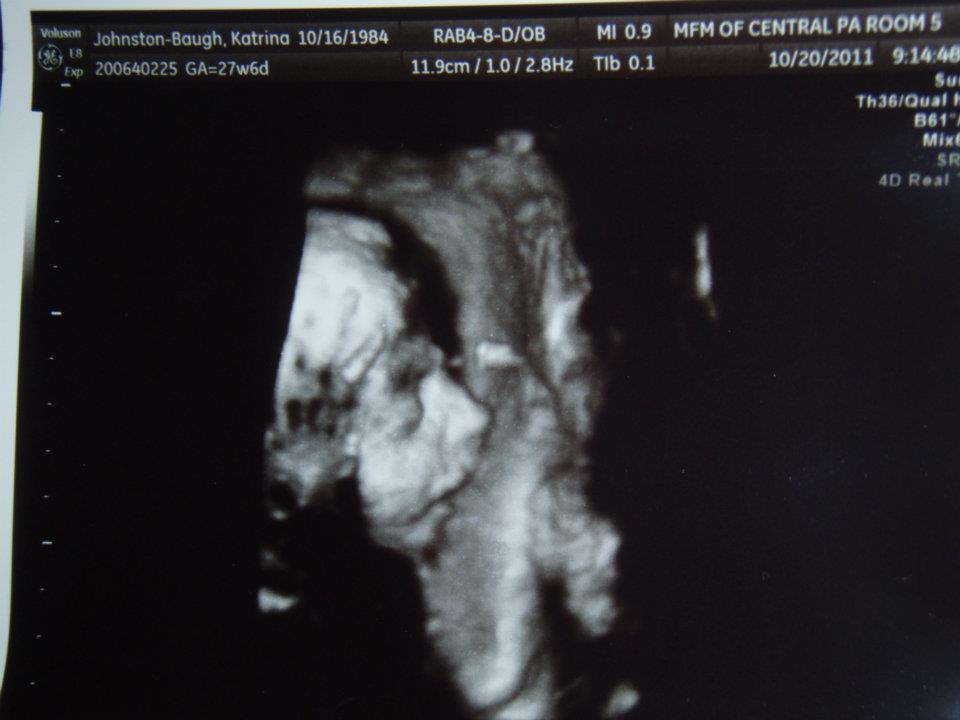

We wanted a simple picture of your face today to make sure you were developing as expected. You didn't allow us to do this 7 weeks ago, but we attributed that to your lack of desire to move to a pathetic apartment. Today, you have no excuse. You were simply being stubborn.

A 25 week, 4 day ultrasound should not take 2 hours. You did not want to face the "camera," and instead hid your sweet face with BOTH hands AND a foot. When the expert tech used her "fool proof" method of getting babes to move by putting the buzzer on my belly, you still didn't budge. She said even she was going to have a choice nickname for you that she couldn't share with us. Now we have to have more ultrasounds in 4 and 8 weeks. This was the first time you embarrassed your parents, but I know it will not be your last.

So, since the tech couldn't get you to move, I had to spank your tiny hind-quarters. This didn't seem to bother you, either. This will have to change once you begin to breathe something other than amniotic fluid.